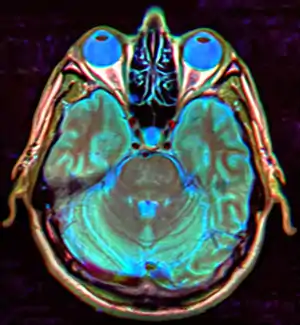

| MRI of Empty Sella | |